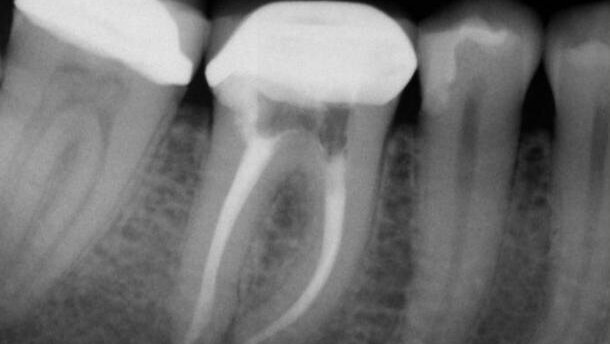

: Obraz po 13 miesiącach obserwacji (leczenie: dr Brett Gilbert).

Jednym z czynników, który zmniejsza szanse powodzenia jest występowanie zapalenia przyzębia wierzchołkowego przed leczeniem. W przypadku braku zapalenia przyzębia wierzchołkowego wskaźnik powodzenia po 10 latach dla pierwotnego leczenia endodontycznego oraz leczenia rewizyjnego wynosił 92-98%. Jeśli przed leczeniem występowało zapalenie tkanek okołowierzchołkowych, wskaźnik powodzenia zmniejszał się, osiągając po 10 latach wartość 74-86%. Na tej podstawie jednoznacznie widać, że możliwe jest uzyskanie wygojenia dzięki rewizji leczenia endodontycznego, co pozwala na zachowanie naturalnych zębów pacjenta (Ryc. 1a-c). Wprawdzie alternatywna metoda leczenia, jaką jest wszczepienie implantu może być skutecznym sposobem zastąpienia brakującego zęba, jednak nadrzędny cel powinno stanowić zachowanie w zdrowiu naturalnych zębów.